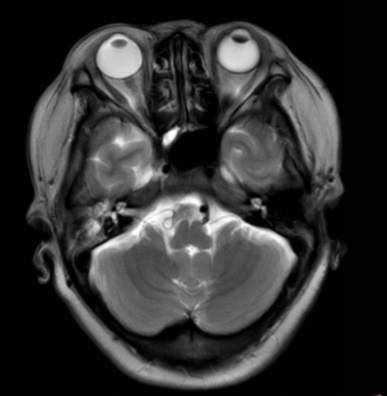

(2023-05-15 10:00,本院)行磁共振(颅脑)检查提示:右侧乳突区异常信号,考虑恶性、软骨来源肿瘤,软骨肉瘤可能性大。(集体讨论意见);脑内散在多发缺血灶。

(2023-05-12 10:15,本院)行CT(颅脑)检查提示:右侧颞骨广泛骨质破坏,伴巨大软组织肿块,性质待定,考虑肿瘤性病变,颈静脉球瘤?软骨源性肿瘤?请结合临床及病理进一步明确。